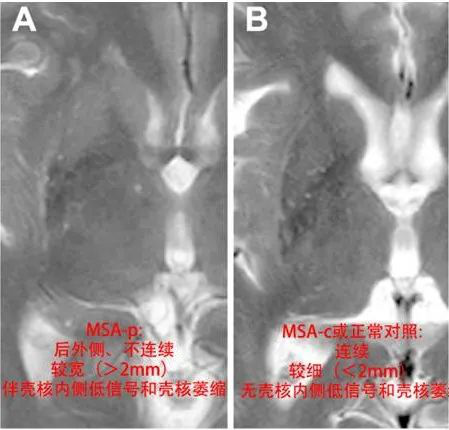

MSA-P 型的 MR 常出現(xiàn):殼核裂隙征、殼核后部 T2 低信號、殼核萎縮。

殼核裂隙征是指殼核外側(cè)邊緣 T2WI 高信號環(huán),MSA-P 型的殼核裂隙多集中在后 半部分,寬度大于 2 mm,存在著不連續(xù)性,存在著附近殼核的低信號,可存在殼核萎縮。MSA-C 型殼核裂隙集中在前半部或前 3/4,并且大部分是連續(xù)性的。

臨床上,約 38.5% 正常人也會出現(xiàn)在 1.5T 或 3.0T 出現(xiàn)殼核外側(cè)線樣 T2WI 高信號,主要集中在前半部或前 3/4,并且大部分是連續(xù)性的,而且寬度在 2 mm 之內(nèi)。大部分不存在殼核的低信號或者只有一部分為輕微的低信號。